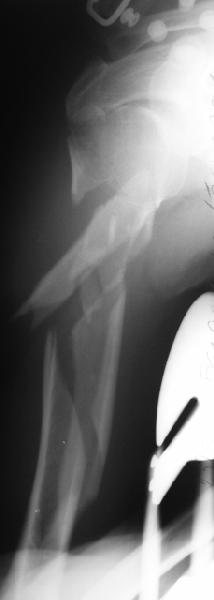

Although we can not see exactly the head piece, and assuming that there are not signs of infection, my suggestion would be to do some type of "bridging" procedure : implant fixation in head piece and distal main fragment, and the rest to be left on its soft tissue attachments (living bone graft).

I just did this attached case, using 90 degrees angled blade plate, and this would be my preference in all similar cases.

• Re: Многооскольчатый перелом плеча

Отправитель: Alexander Chelnokov 05 Октябрь 2003, 13:41

1

2

EKTE> rest to be left on its soft tissue attachments (living bone graft).

EKTE> I just did this attached case, using 90 degrees angled blade plate, and

EKTE> this would be my preference in all similar cases.

We don't even have so long plates in stock...

Well, to date he is still on abduction splint with traction applied to a wire placed through the olecranon. Images attached. The acetabulum

was ORIFed. The humerus is still discussing...

The views you now show demonstrate an extra articular fracture with good alignment on the AP, and some displacement on the lateral.

This should be able to be managed with adjustment of the traction.

Ilizarov is probably the best fixation if you decide to do so. However, it will heal with nonoperative treatment, with painless, reasonable

function. Even if it does not heal primarily, the pieces will heal enough to become a single level problem, readily solved with compression

plating. Jim Carr